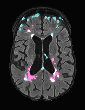

In recent years, data-driven machine learning (ML) methods have revolutionized the computer vision community by providing novel efficient solutions to many unsolved (medical) image analysis problems. However, due to the increasing privacy concerns and data fragmentation on many different sites, existing medical data are not fully utilized, thus limiting the potential of ML. Federated learning (FL) enables multiple parties to collaboratively train a ML model without exchanging local data. However, data heterogeneity (non-IID) among the distributed clients is yet a challenge. To this end, we propose a novel federated method, denoted Federated Disentanglement (FedDis), to disentangle the parameter space into shape and appearance, and only share the shape parameter with the clients. FedDis is based on the assumption that the anatomical structure in brain MRI images is similar across multiple institutions, and sharing the shape knowledge would be beneficial in anomaly detection. In this paper, we leverage healthy brain scans of 623 subjects from multiple sites with real data (OASIS, ADNI) in a privacy-preserving fashion to learn a model of normal anatomy, that allows to segment abnormal structures. We demonstrate a superior performance of FedDis on real pathological databases containing 109 subjects; two publicly available MS Lesions (MSLUB, MSISBI), and an in-house database with MS and Glioblastoma (MSI and GBI). FedDis achieved an average dice performance of 0.38, outperforming the state-of-the-art (SOTA) auto-encoder by 42% and the SOTA federated method by 11%. Further, we illustrate that FedDis learns a shape embedding that is orthogonal to the appearance and consistent under different intensity augmentations.